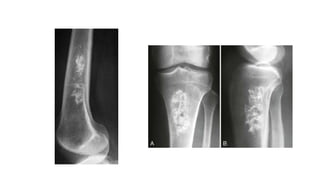

Osteoid osteoma

 I

s a painful condition found most commonly in the femur and

tibia in young adults.

 Characteristic radiological appearance: a small lucency,

sometimes with central specks of calcification, known as a

nidus, surrounded by dense sclerotic rim.

 A periosteal reaction may also be present.

 Radionuclide bone scanning:shows marked focal increased

activity.

Osteoid osteoma  I sa painful condition found most commonly in the femur and tibia in young adults.  Characteristic radiological appearance: a small lucency, sometimes with central specks of calcification, known as a nidus, surrounded by dense sclerotic rim.  A periosteal reaction may also be present.  Radionuclide bone scanning:shows marked focal increased activity.